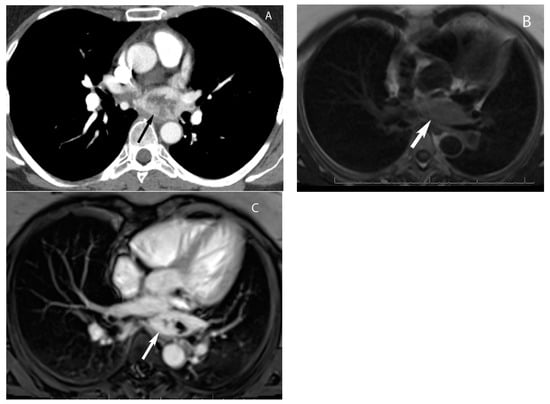

7. Germ Cell Tumors

9. Hypervascular Lesions